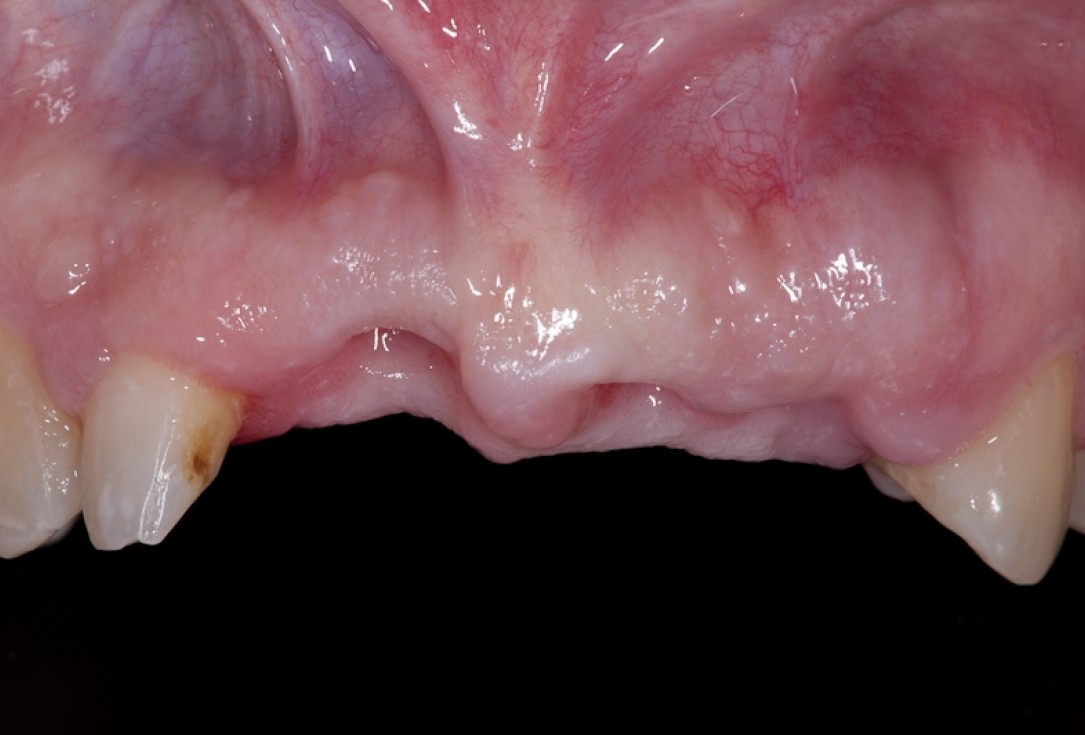

Situation after tooth extraction.